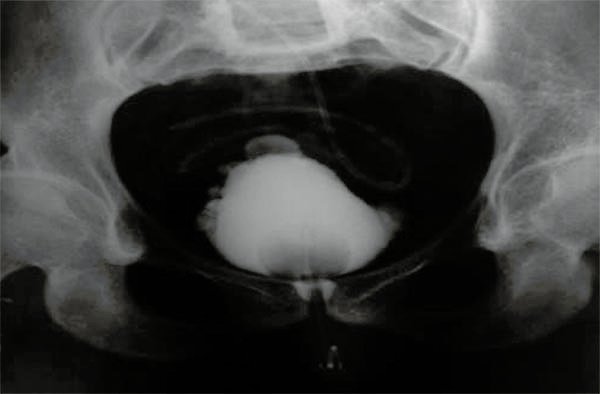

Paciente de sexo femenino de 34 años de edad con MMC Grado 3. Defecto del tubo neural corregido a las 6 horas de vida e hidrocefalia tratada con una derivación ventriculoperitoneal a los 12 meses de vida. No efectuaba cateterismo. Urograma excretor: normal. Incontinencia fecal y urinaria. Siempre uso pañales. A los 22 años de edad se realizó cistografía retrógrada con resultado patológico (fig. 2).

Figura 2:

Cistografía paciente n°3.